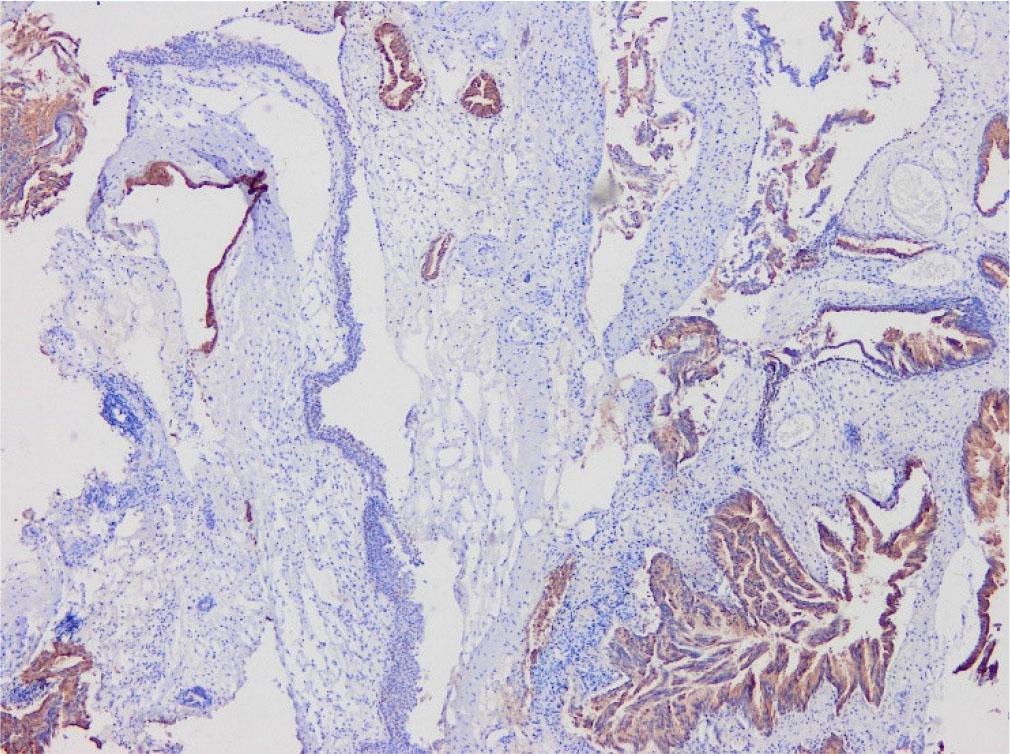

Fig. 3-